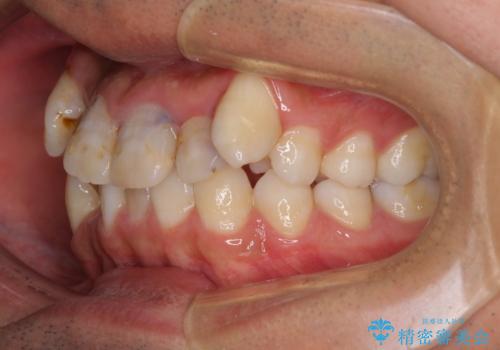

前歯の歯列が整ったことで、歯磨きが大変やりやすくなり、患者様には大変満足していただけました。

上下ともに八重歯が顕著であったため、上下左右の第一小臼歯4本を抜歯し、ワイヤー装置での抜歯矯正を行うこととしました。

前歯は根管治療が必要な歯を事前に根管治療を行い、矯正治療後にオールセラミッククラウンにて補綴治療を行うこととしました。